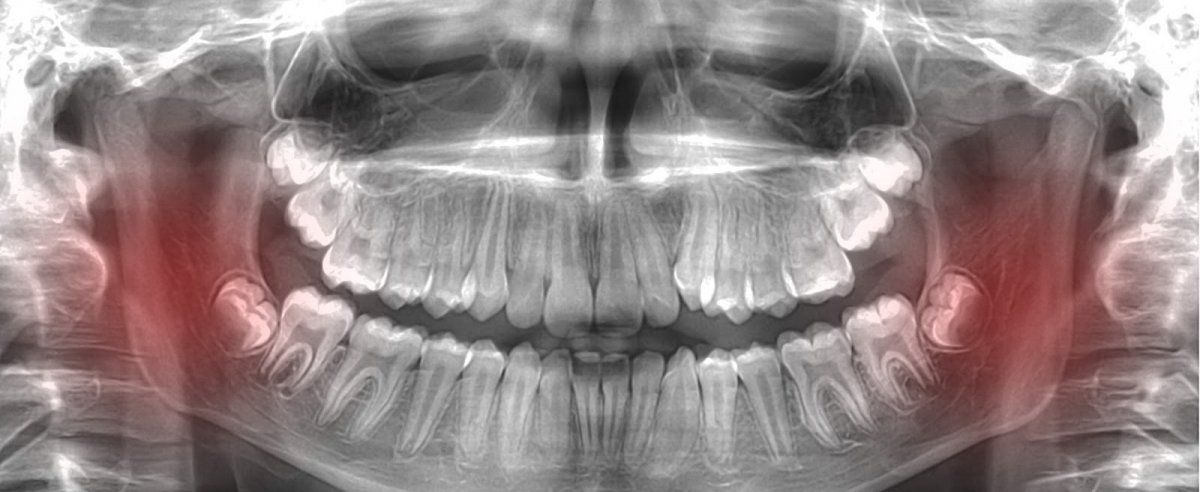

La articulación de la mandíbula o articulación temporomandibular se compone por los huesos que forman, por un lado, la propia mandíbula y por otra, aquellos que se sitúan justo por encima de la boca (el maxilar).

Estos serían algunos indicadores que nos alertarían de un problema en la articulación temporomandibular:

La osteomielitis es una infección que se origina en la propia articulación de la mandíbula.

Un absceso dental se origina también por una infección, pero esta vez el se localiza en la pulpa dental o e un nervio.